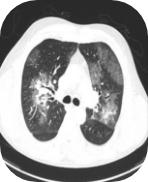

Chest computerised tomography (CT):

Bilateral ground glass opacities and a small

consolidation in the left lower lung lobe

Images supplied with permission of treating clinician.